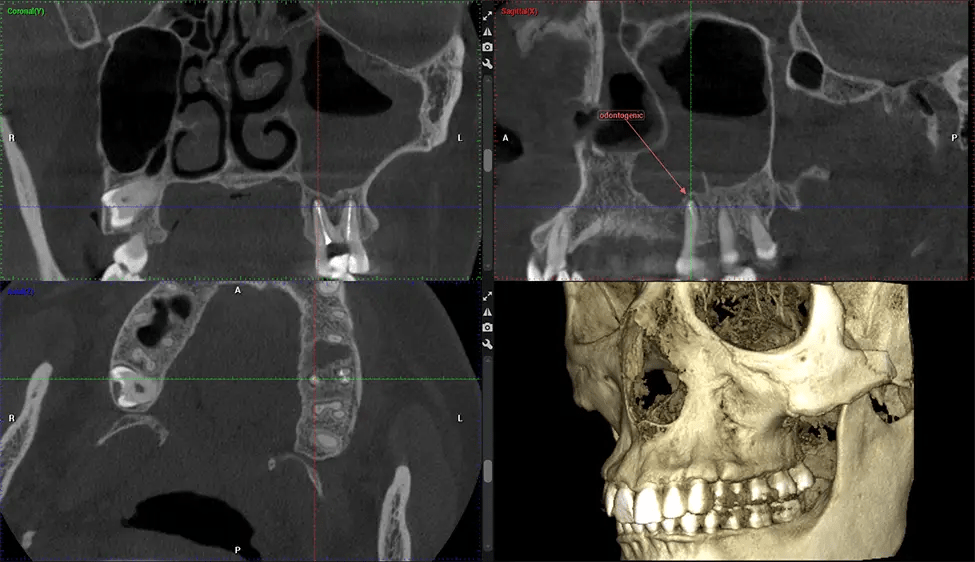

This 3D scan, called cone beam computed tomography, gives your dentist a more complete image of your oral anatomy and disease processes than a traditional X-ray. Unlike conventional X-rays, which capture a 2D image of your mouth from various angles, a 3D scan takes multiple digital X-rays for one image. It provides a complete view of your jaw, teeth, nerves, and soft tissues. This enhanced view allows dentists to detect minor issues not visible in traditional 2D scans, such as impacted wisdom teeth or bone fractures in the sinus cavity.

There are many benefits to using CBCT technology, especially compared to the traditional 2D X-ray format. One of the most significant advantages of CBCT scans is that they provide much more information than traditional X-rays. A scan lets your dentist see images from all angles of your jaw and mouth, including your sinuses, nasal cavity, cheekbones, and other surrounding areas. This added information helps your dentist craft a comprehensive treatment plan that addresses all aspects of your oral health.

Another significant benefit is that 3D imaging provides more precise images of your bone structure. These images are more detailed, providing you with a more accurate diagnosis. An accurate diagnosis means better treatment for you.

When paired with extractions, dental implant placement, or bone grafting, CBCT technology can provide you with a quicker and much more comfortable experience. This is because the 3D image provides a more detailed picture of your entire oral cavity, allowing your dentist to walk you through each step of the process before it occurs. This often helps patients feel more prepared and comfortable overall, especially if they have had a traumatic experience with past dental treatments.